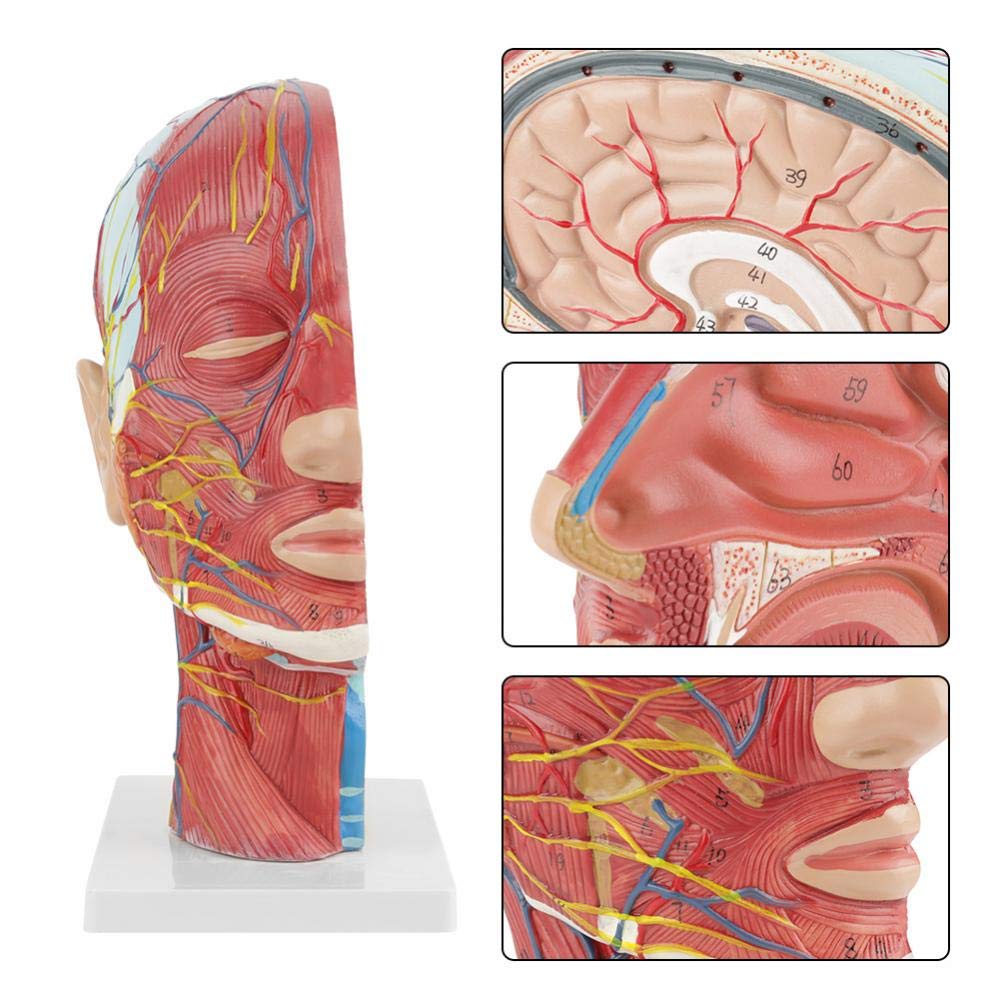

| Awọn ẹya | Awoṣe naa fihan ọrọ ayọ ti agbegbe ti apakan ti inu ati ọrun, ati awọn ẹya ara ti awọn iṣan ara ati awọn ẹya ara, ati awọn ẹya 84 wa ti o nfihan awọn ami lapapọ. |

Ni 1: 1 LIGESED】 Mediani Akan Media ti 1: 1 ori nla ti o tobi julọ & ade nla ti iṣan iṣan ti iṣan ti o ni iṣan iṣan. Iṣẹ adaṣe daradara. Nfunni ni kikun ti awọn ẹya anatomical.

Awoṣe iṣan iṣan】 alaye ti o ga pupọ, awọn nọmba ti samisi, jinlẹ ti awọn iṣan to loye awọn iṣan ati ọrun inu & ọrùn ti ori & ọrun. Atter-mq-iṣọn, buluu-vening, alawọ ofeefee.

Awọn ẹya】 o ṣafihan awọn iṣan ti o fara ara ti oju ti o farabalẹ; Awọn ohun elo ẹjẹ ti o dara julọ & awọn iṣan ti oju & scalp; Awọn ẹya inu ti Patiod erumlandi ati oke atẹgun; Eto apakan-ilẹ Sagittal artical ti ọpa ẹhin.

Awoṣe yii fihan awọn alaye ti ọrun-ọrun ati apakan sagittital ti eniyan. pẹlu superficial

awọn iṣan ti oju oju; Awọn ohun elo ẹjẹ ti o ga julọ ati awọn iṣan oju ti oju ati awọsanma; Awọn ẹya inu

ti parotid blandi ati atẹgun oke; Eto apakan-ilẹ Sagittal artical ti ọpa ẹhin.

Awoṣe ṣe afihan ọrọ-ọrọ ti agbegbe ti aarin ati awọn apakan sagittal ita ti ori ati ọrun ati awọn ẹya ara ati awọn ẹya ara ẹrọ ti ofura, pẹlu apapọ awọn olufihan oju opo wẹẹbu 100.

Awoṣe yii jẹ ori ti o tobi pupọ ati awoṣe iṣan ti o ni agbara nla ati eto aarin ti ẹṣẹ parotid ati atẹgun oke, ati apakan apakan apakan Sagitttal ti ọpa ẹhin